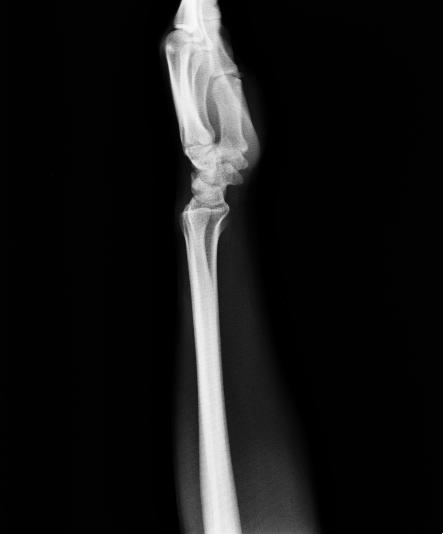

以下是引用杀毒软件在2008-9-4 17:41:00的发言:[br]考虑----舟骨囊肿